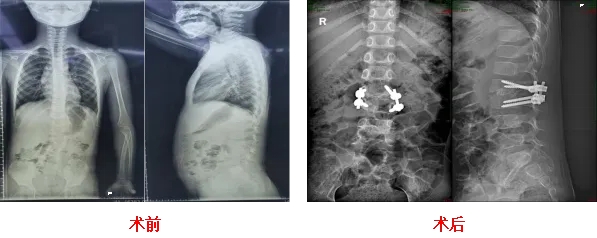

近期半椎体畸形矫正手术

CASE 2